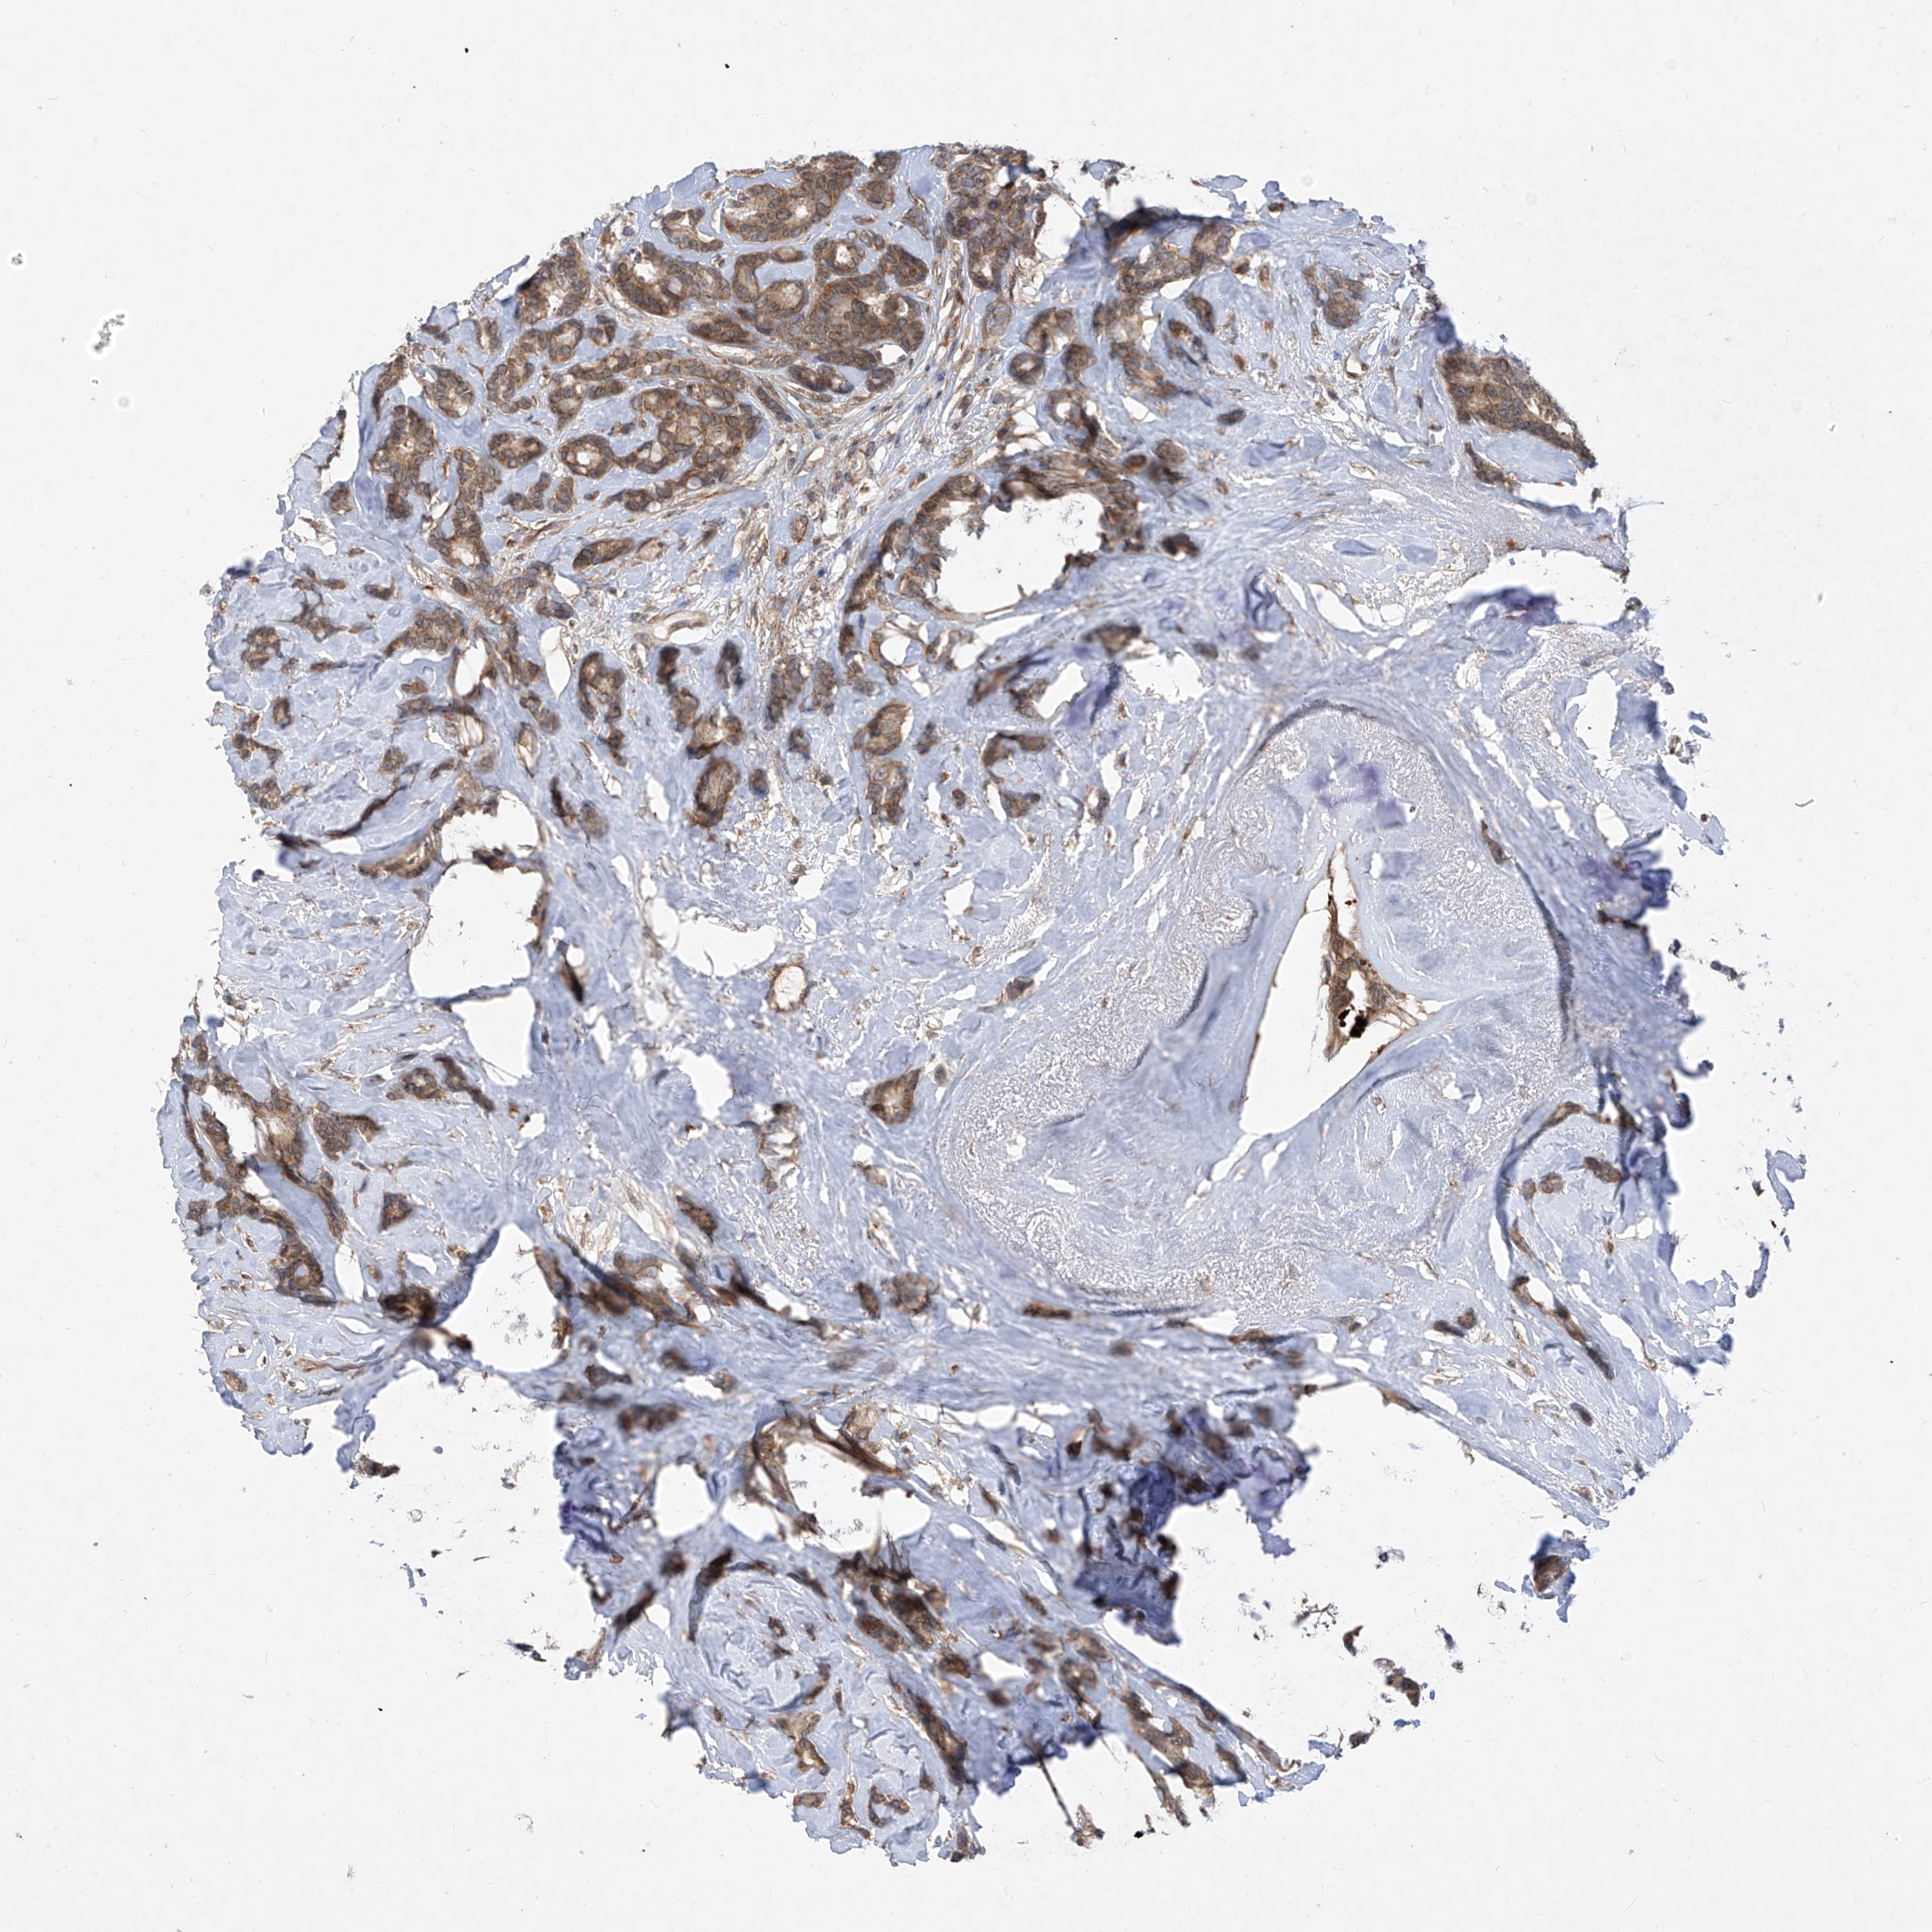

CANCER BREAST CANCER Show tissue menu

BRCA TCGA BRCA VALIDATION PROTEIN EXPRESSION